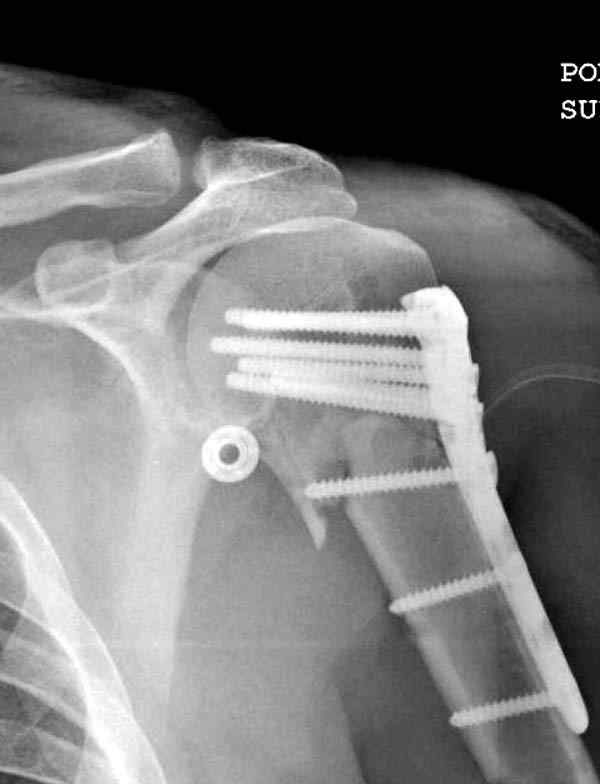

Здесь пример открытой репозиции 57 летнего с переломом плеча (1,2) смещение обнаружено на интероперационном снимке. При нормальной прямой проекция (3) угловое смещение обнаружили в аксиальной проекции (4)

После устранения смещения пластина установлена выше (5,6,7) и финальные снимки (8,9,10)

Подбор импланта тоже имеет значение, например многие импланты направлены для фиксации перелома без учета ротаторной манжетки. Предпочтительными являются низко сидящие полиаксиальные пластины, где верхние шурупы можно проводить под углом в 120 градусов. (11)

Пластина от Synthes или ее копии (надеюсь простят критику друзья из Деоста) считаются трудным из-за обширности доступа, особенно при установке верхне-заднего шурупа, где доступ надо расширять в верхнем отделе до ротаторной манжетки. Верхне сидящие импланты предназначены для проведения опоры (buttress) за бугристость плеча, но тогда приходится сталкиваться с подакромиальным импинжментом.